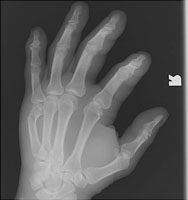

So named because of the common occurrence in prizefighters, the fracture involves the distal metacarpal neck, usually of digit five. The distal fracture fragment is volarly angulated and may be externally rotated. The injury results from direct trauma to the hand.

- Click on the image for a larger versionAPA radiograph of the hand. This is the typical appearance of a boxer's fracture with volar angulation of the distal fracture fragment.